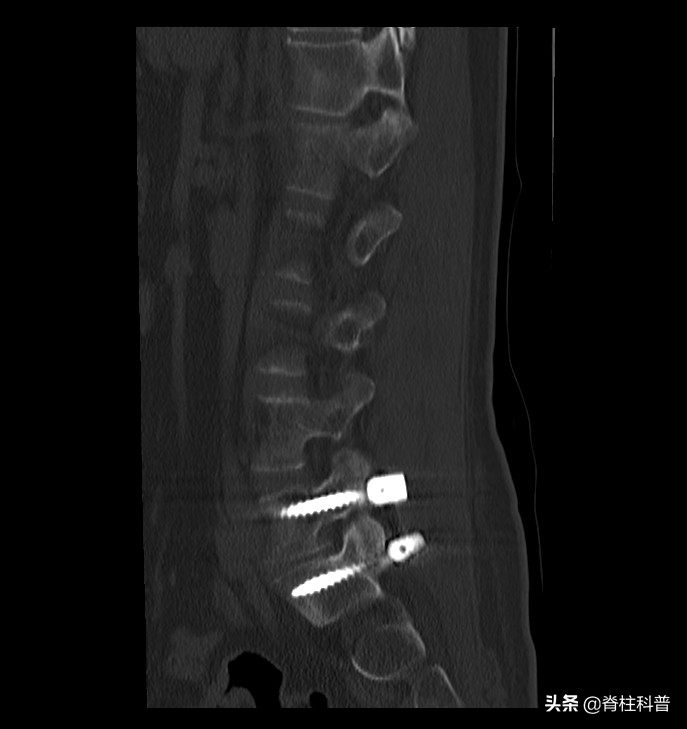

扫描快速费用较低的CT是腰椎间盘突出症患者首选方式。

CT也是临床中多种疾病诊断的常用影像学检查方式,具有扫描区域广、速度快、费用低的特点,是很多腰椎间盘突出患者首选的诊断方式。

CT能够清晰显示椎体情况、腰椎间隙内部情况,以便掌握脊髓内是否存在肿瘤、结核等病症,还有助于对腰骶椎后位、斜位状况进行评定,另外在腰椎间盘突出钙化和积气等方面有着较高的灵敏度,能显示周围组织和病变髓核之间的关系,对神经根受压情况的诊断有重要意义。

CT检查也存在着一定的不足之处,如仪器种类较多,不同的仪器在扫描技术方面存在较大差异,诊断的误差较大,对影像学医师的要求也更高(没有经验的医师容易将突出诊断为膨出)。对严重脊柱畸形、先天性椎管狭窄及椎管术后、椎间盘游离、椎间盘钙化等方面效CT诊断有一定困难。而且CT存在一定的放射性。

术后CT片子